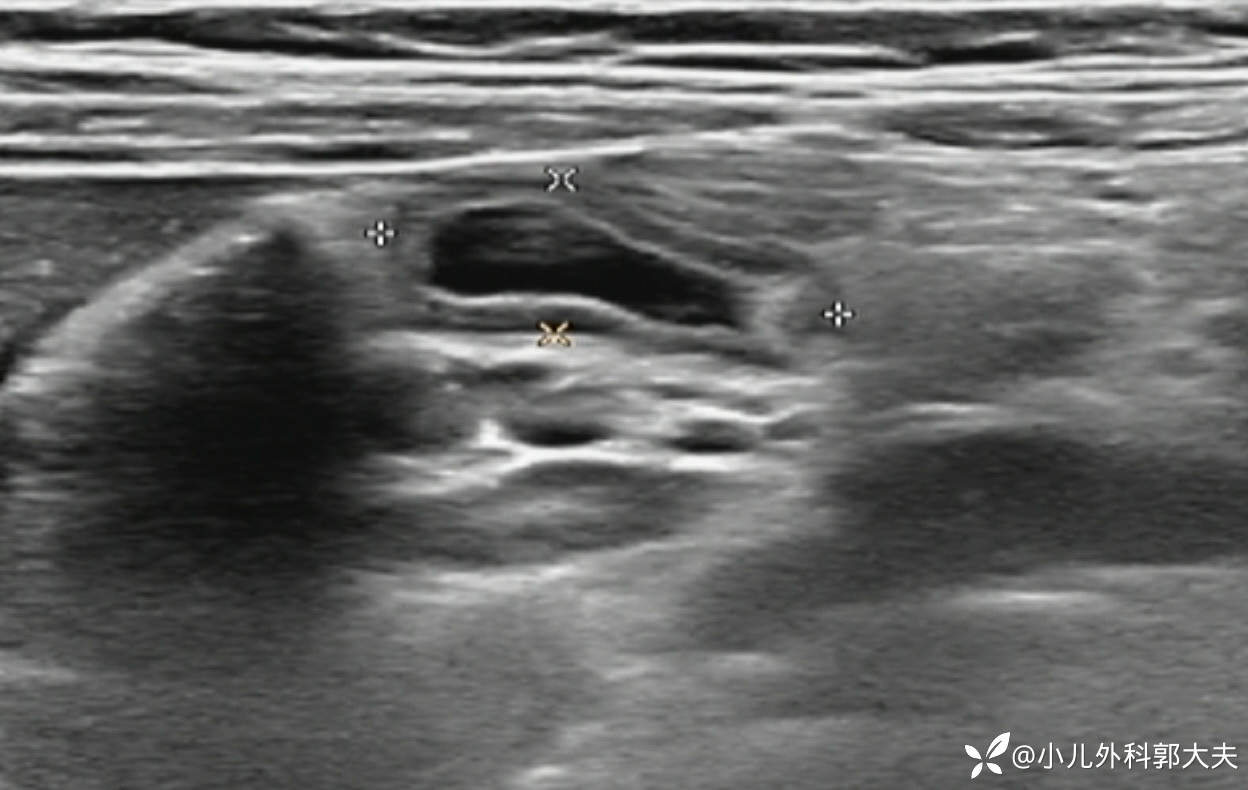

超声提示右下腹异常肠管回声